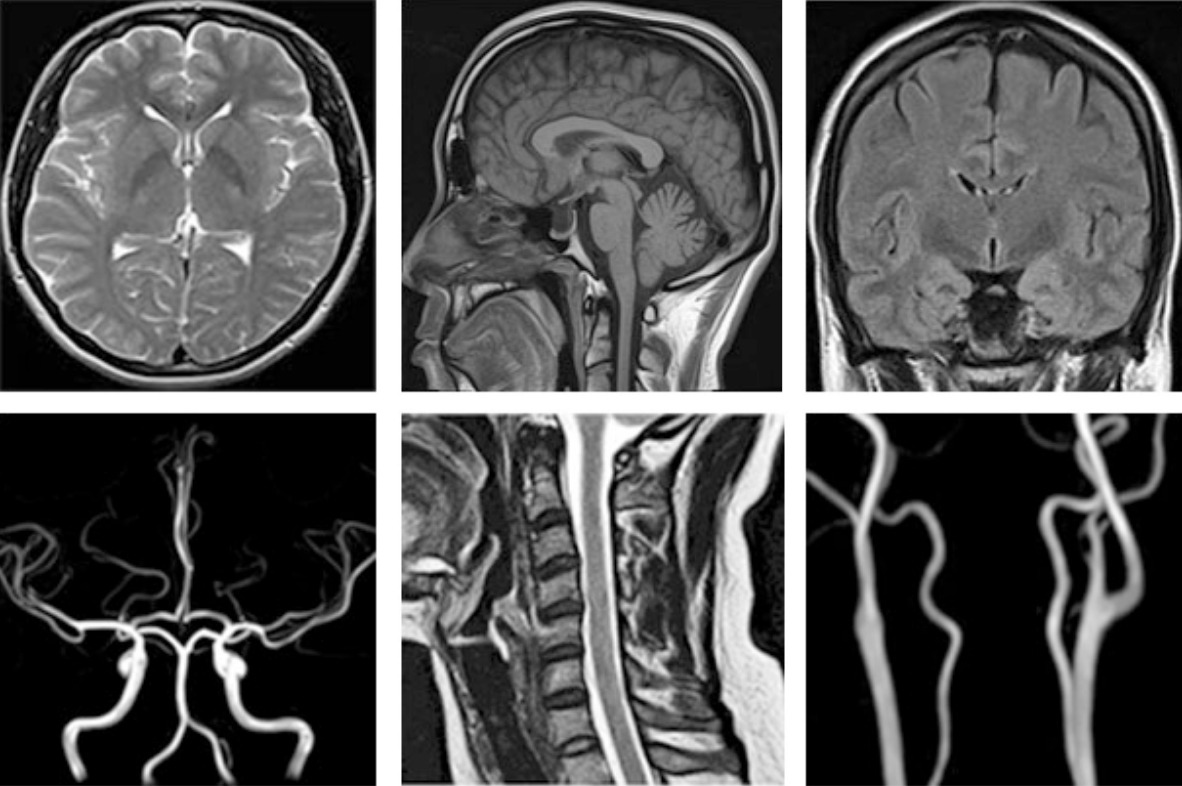

- 조영제 사용 목적

- 종양이나 염증 등 특정 병변을 더 명확하게 보기 위해 시행

- MRI 장비 성능(1.5T, 3.0T 여부)

- 촬영 범위(뇌 단독, 뇌·경추 동시 촬영 등)